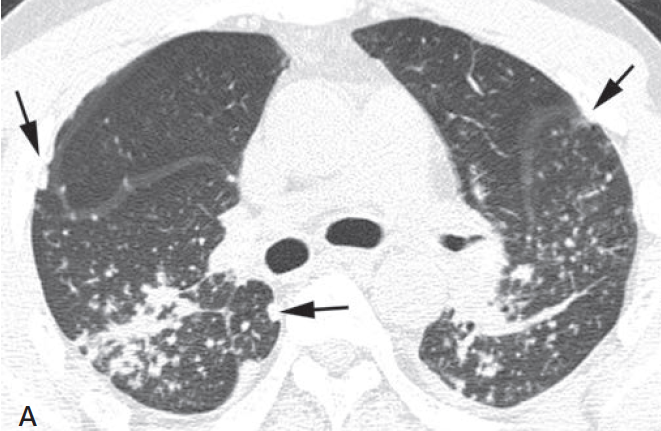

Silicose simple

- Nodules centrolobulaires + sous-pleuraux (sarcoïdose = péribronchovasculaire + scissural)

- Parfois pseudoplaques sous pleurales

- Prédominants aux lobes supérieurs

- Pas de fibrose

- ADP en coquille d’oeuf (suggestif, non specique), plus fréquement encore celles avec calcifications ponctiformes

- De multiples nodules de silicose peuvent mimer une miliaire

Nodules périlymphatiques, centrolobulaires, sous-pleuraux (pseudoplaques)